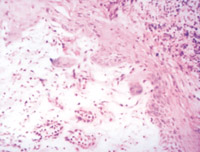

5-2-3 傷后第3天,表皮細(xì)胞空泡化,真皮淺層膠原纖維玻璃樣變,真皮內(nèi)散在炎細(xì)胞浸潤(rùn)  HE×100